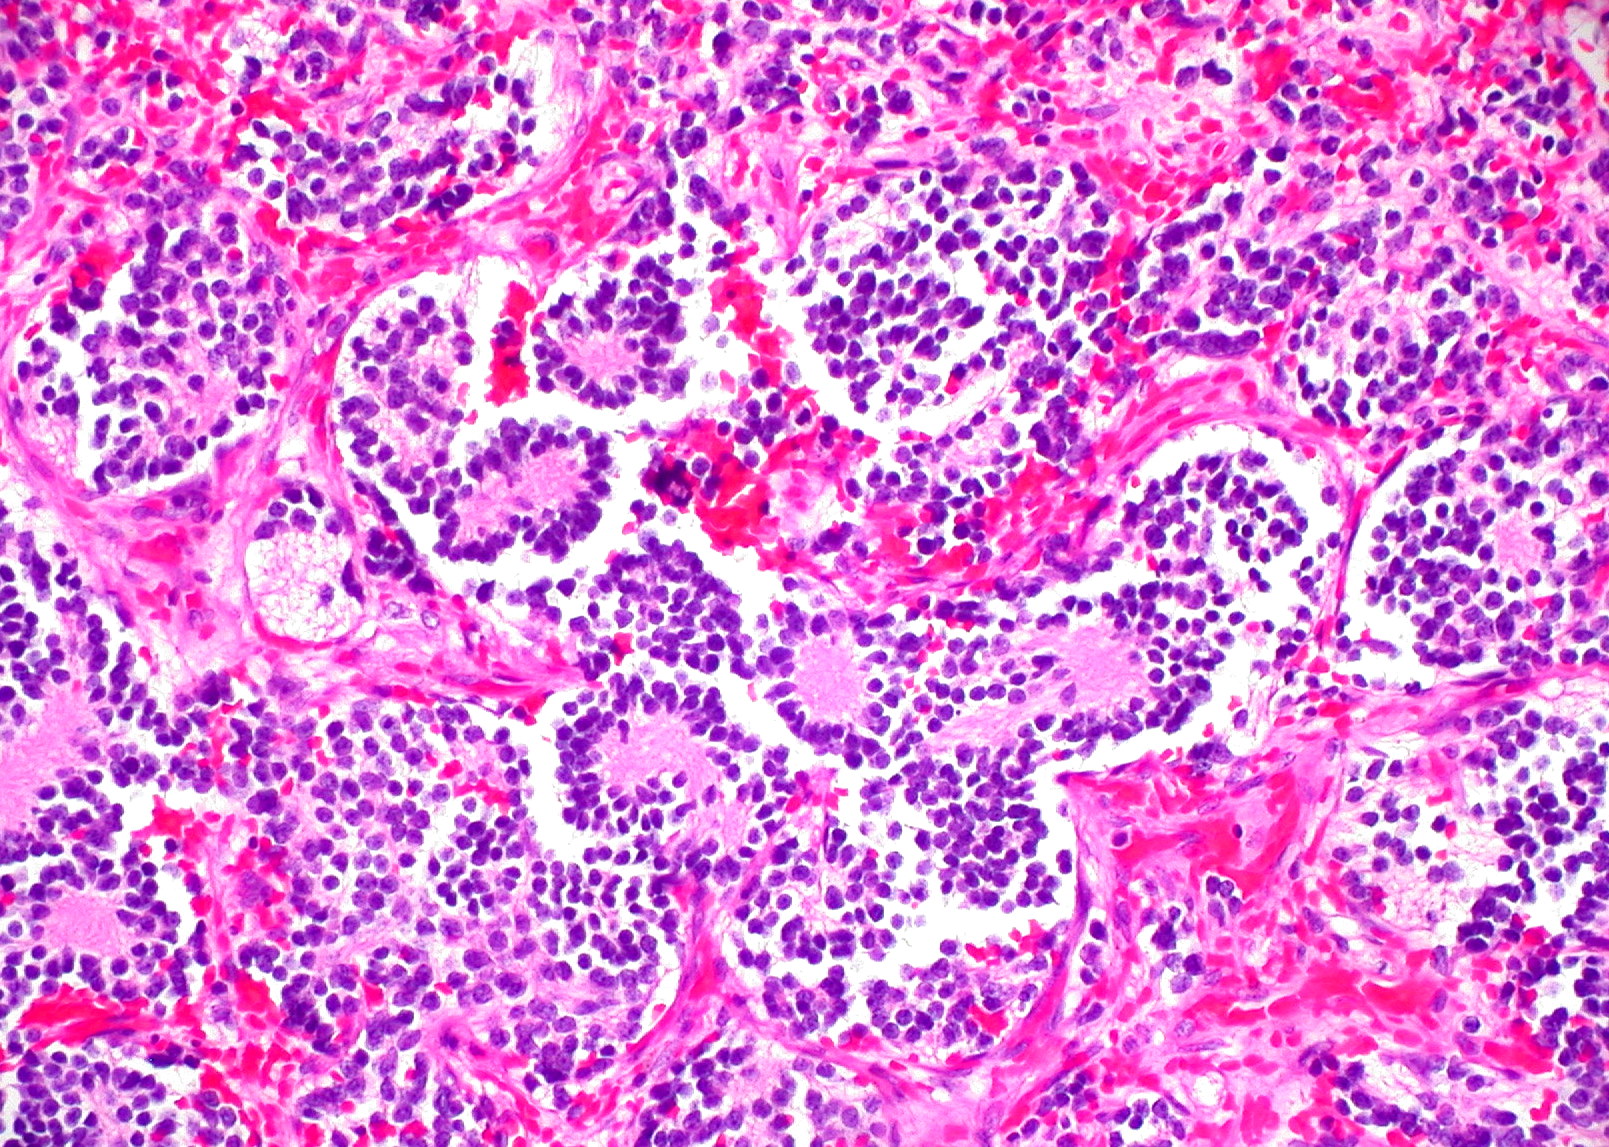

El neuroblastoma es un tipo de tumor sólido poco frecuente que suele afectar a niños y es una enfermedad difícil de tratar, con altas tasas de recaída a pesar del tratamiento. El equipo del Baylor College, liderado por Helen Heslop, llevó a cabo un ensayo clínico de fase 1 con 19 niños con neuroblastoma, entre 2004 y 2009, en el que probaron células T modificadas para reconocer GD2, una proteína con altos niveles de expresión en el neuroblastoma.